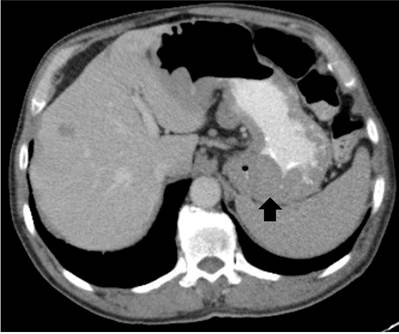

Con sospecha de trastorno linfoproliferativo se realiza tomografía (TC) de cuello, abdomen y pelvis contrastadas, con hallazgo de hipertrofia amigdalina, que condiciona el cierre del 70% de la orofaringe, extenso compromiso por adenopatías en cadenas ganglionares cervicales, axilares, mediastinales, con conglomerado ganglionar subcarinal, con efecto obstructivo sobre bronquios fuente, retroperitoneales y engrosamiento de las paredes gástricas (Figura 1).